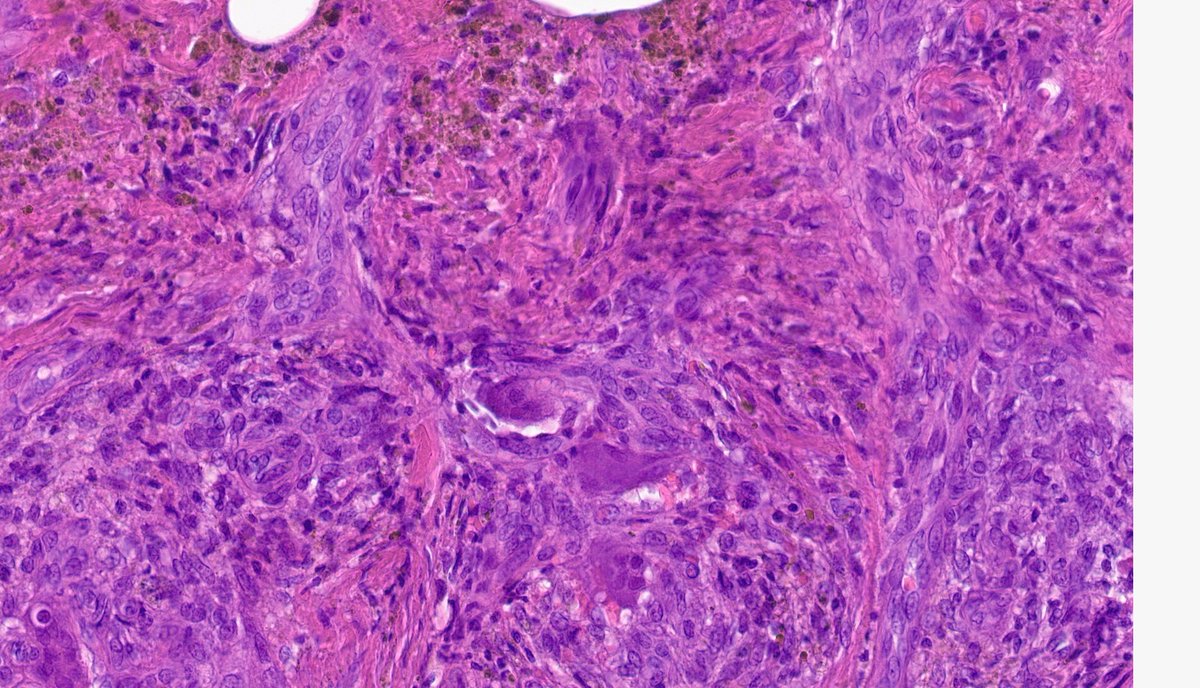

Middle-aged female. Let's play the #tooclosetodiagnose game. Hit me with your excellent differentials 😎 #PathTwitter folks. Annamária Ribiánszky, MD Dan Graham Immanuel Paul Kenny De Gracia T.